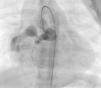

Os motivos de referência mais frequentes foram sopro e/ou cansaço. Todas as fístulas eram de origem congénita. Cinco doentes (42%) tinham patologia cardíaca concomitante: atrésia da pulmonar com septo interventricular intacto (1), canal arterial persistente (1), comunicação interauricular ostium secundum (1), estenose aórtica em válvula aórtica biscúspide (1), estenose pulmonar crítica operada no período neonatal (1). Foram realizadas angiografias selectivas para delinear a anatomia da(s) fístula(s). A embolização foi feita na porção mais distal da fístula, poupando todos os ramos colaterais. Num doente foi realizada uma ansa arteriovenosa através da fístula, com embolização da porção terminal da fístula a partir da aurícula direita. Os doentes foram heparinizados (100 U.I./kg na criança e 5000 U.I. no adulto) e foi feito o controlo posterior através do valor de ACT. Três dos doentes apresentavam duas fístulas e os restantes comunicações fistulosas isoladas. As fístulas eram todas hemodinamicamente significativas e tinham origem no território da coronária direita (n=10), da coronária esquerda (n=3) e da circunflexa (n=2) e drenavam para o ventrículo direito (n=5), artéria pulmonar (n=6), aurícula direita (n=2), seio coronário (n=1) e ventrículo esquerdo (n=1). O material de embolização incluiu 15 coils standard em 3 doentes, 1 coil Jackson® num doente (Figuras 1–3), 27 microcoils em 11 doentes (18 microcoils simples em 7 doentes e 9 microcoils GDC em 4 doentes) e um dispositivo Amplatzer®Duct Occluder num doente (Figuras 4–7). Merece um destaque especial os microcoils GDC, simples ou complexos, que são dispositivos de libertação controlada por electrólise, o que permite que o procedimento seja reversível até à fase final da libertação, após se confirmar a boa posição do dispositivo. Num doente foi testado um plug cardíaco Amplatzer® que não foi libertado por não ser adequado à lesão.